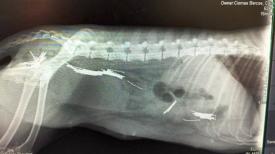

În rechizitoriul magistraţilor se arată că „organele de poliţie din cadrul Postului de Poliţie Lumina au fost sesizate de către un martor ocular, cu privire la faptul că în aceeaşi localitate, trei persoane de sex bărbătesc au lovit un câine fără stăpân cu o lopată şi au asmuţit un alt câine de luptă asupra sa, până ce acesta nu a mai mişcat, iar ulterior l-au introdus într-un sac şi apoi în portbagajul unui autoturism, părăsind locul faptei. Procurorii mai arată că animalul fără stăpân a fost lovit în repetate rânduri cu o lopată, iar câinele de luptă, fără botniţă, ţinut în lesă, la comanda unuia dintre inculpaţi, a atacat şi muşcat de gât câinele fără stăpân.